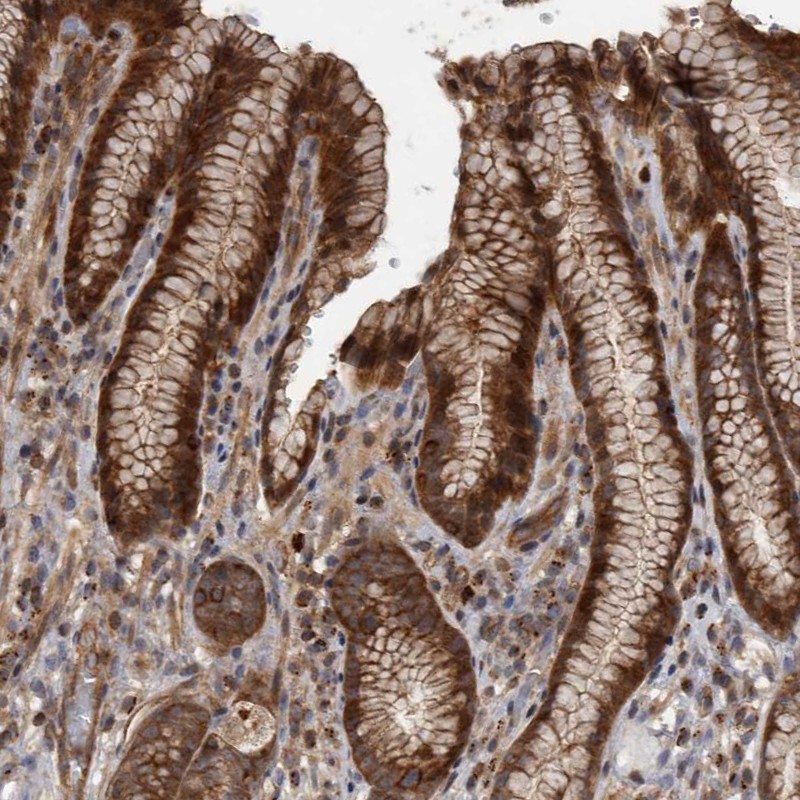

Immunohistochemical staining of human stomach shows strong cytoplasmic positivity in glandular cells.